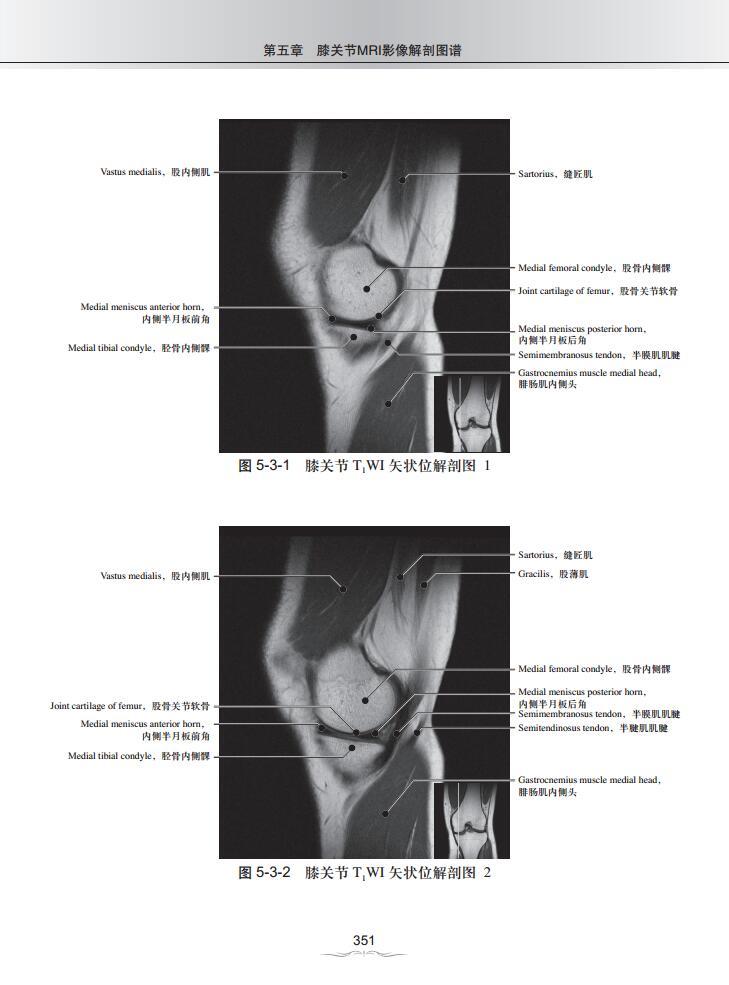

第五章 膝关节MRI影像解剖图谱

三、T1WI矢状位解剖图